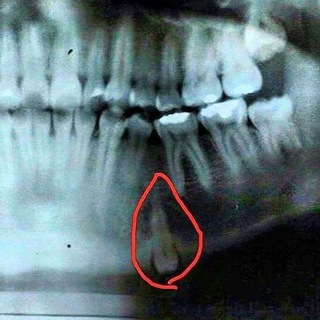

Канал посвященный Гнатологии и современному подходу BUDOVSKY Подкасты Доктора Будовского #пдкст_BUDOVSKY Отзывы пациентов #улыбка_BUDOVSKY